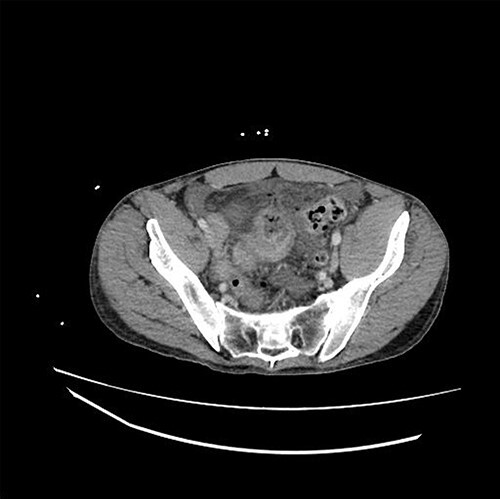

The patient is a 31-year-old male with medical history significant for EDS Type IV who presented for evaluation of sudden onset of abdominal pain, which woke him from sleep. He had a medical history significant of mitral valve prolapse and prior bacterial endocarditis resulting in bovine pericardial mitral valve replacement (MVR) on Coumadin, hemorrhagic left parietal stroke, history of ventilator dependent respiratory failure s/p tracheostomy and percutaneous endoscopic gastrostomy tube (PEG) with subsequent decannulation and removal. Current medications included aspirin 81 mg, warfarin, furosemide, Lisinopril, metoprolol and fluoxetine. Admission vital signs were unremarkable. Physical exam revealed a distended, diffusely tender abdomen with involuntary guarding. The lab values were significant of a leukocytosis of 18.53, INR 2.50 and lactic acid of 2.7. A computed tomography scan of the abdomen and pelvis with intravenous contrast demonstrated a dilated loop of distal ileum with associated mucosal thickening, free air and free fluid concerning for bowel perforation (Fig. 1).

Figure 1.

CT demonstrating thickened loop of ileum in the pelvis with pneumoperitoneum and free fluid.